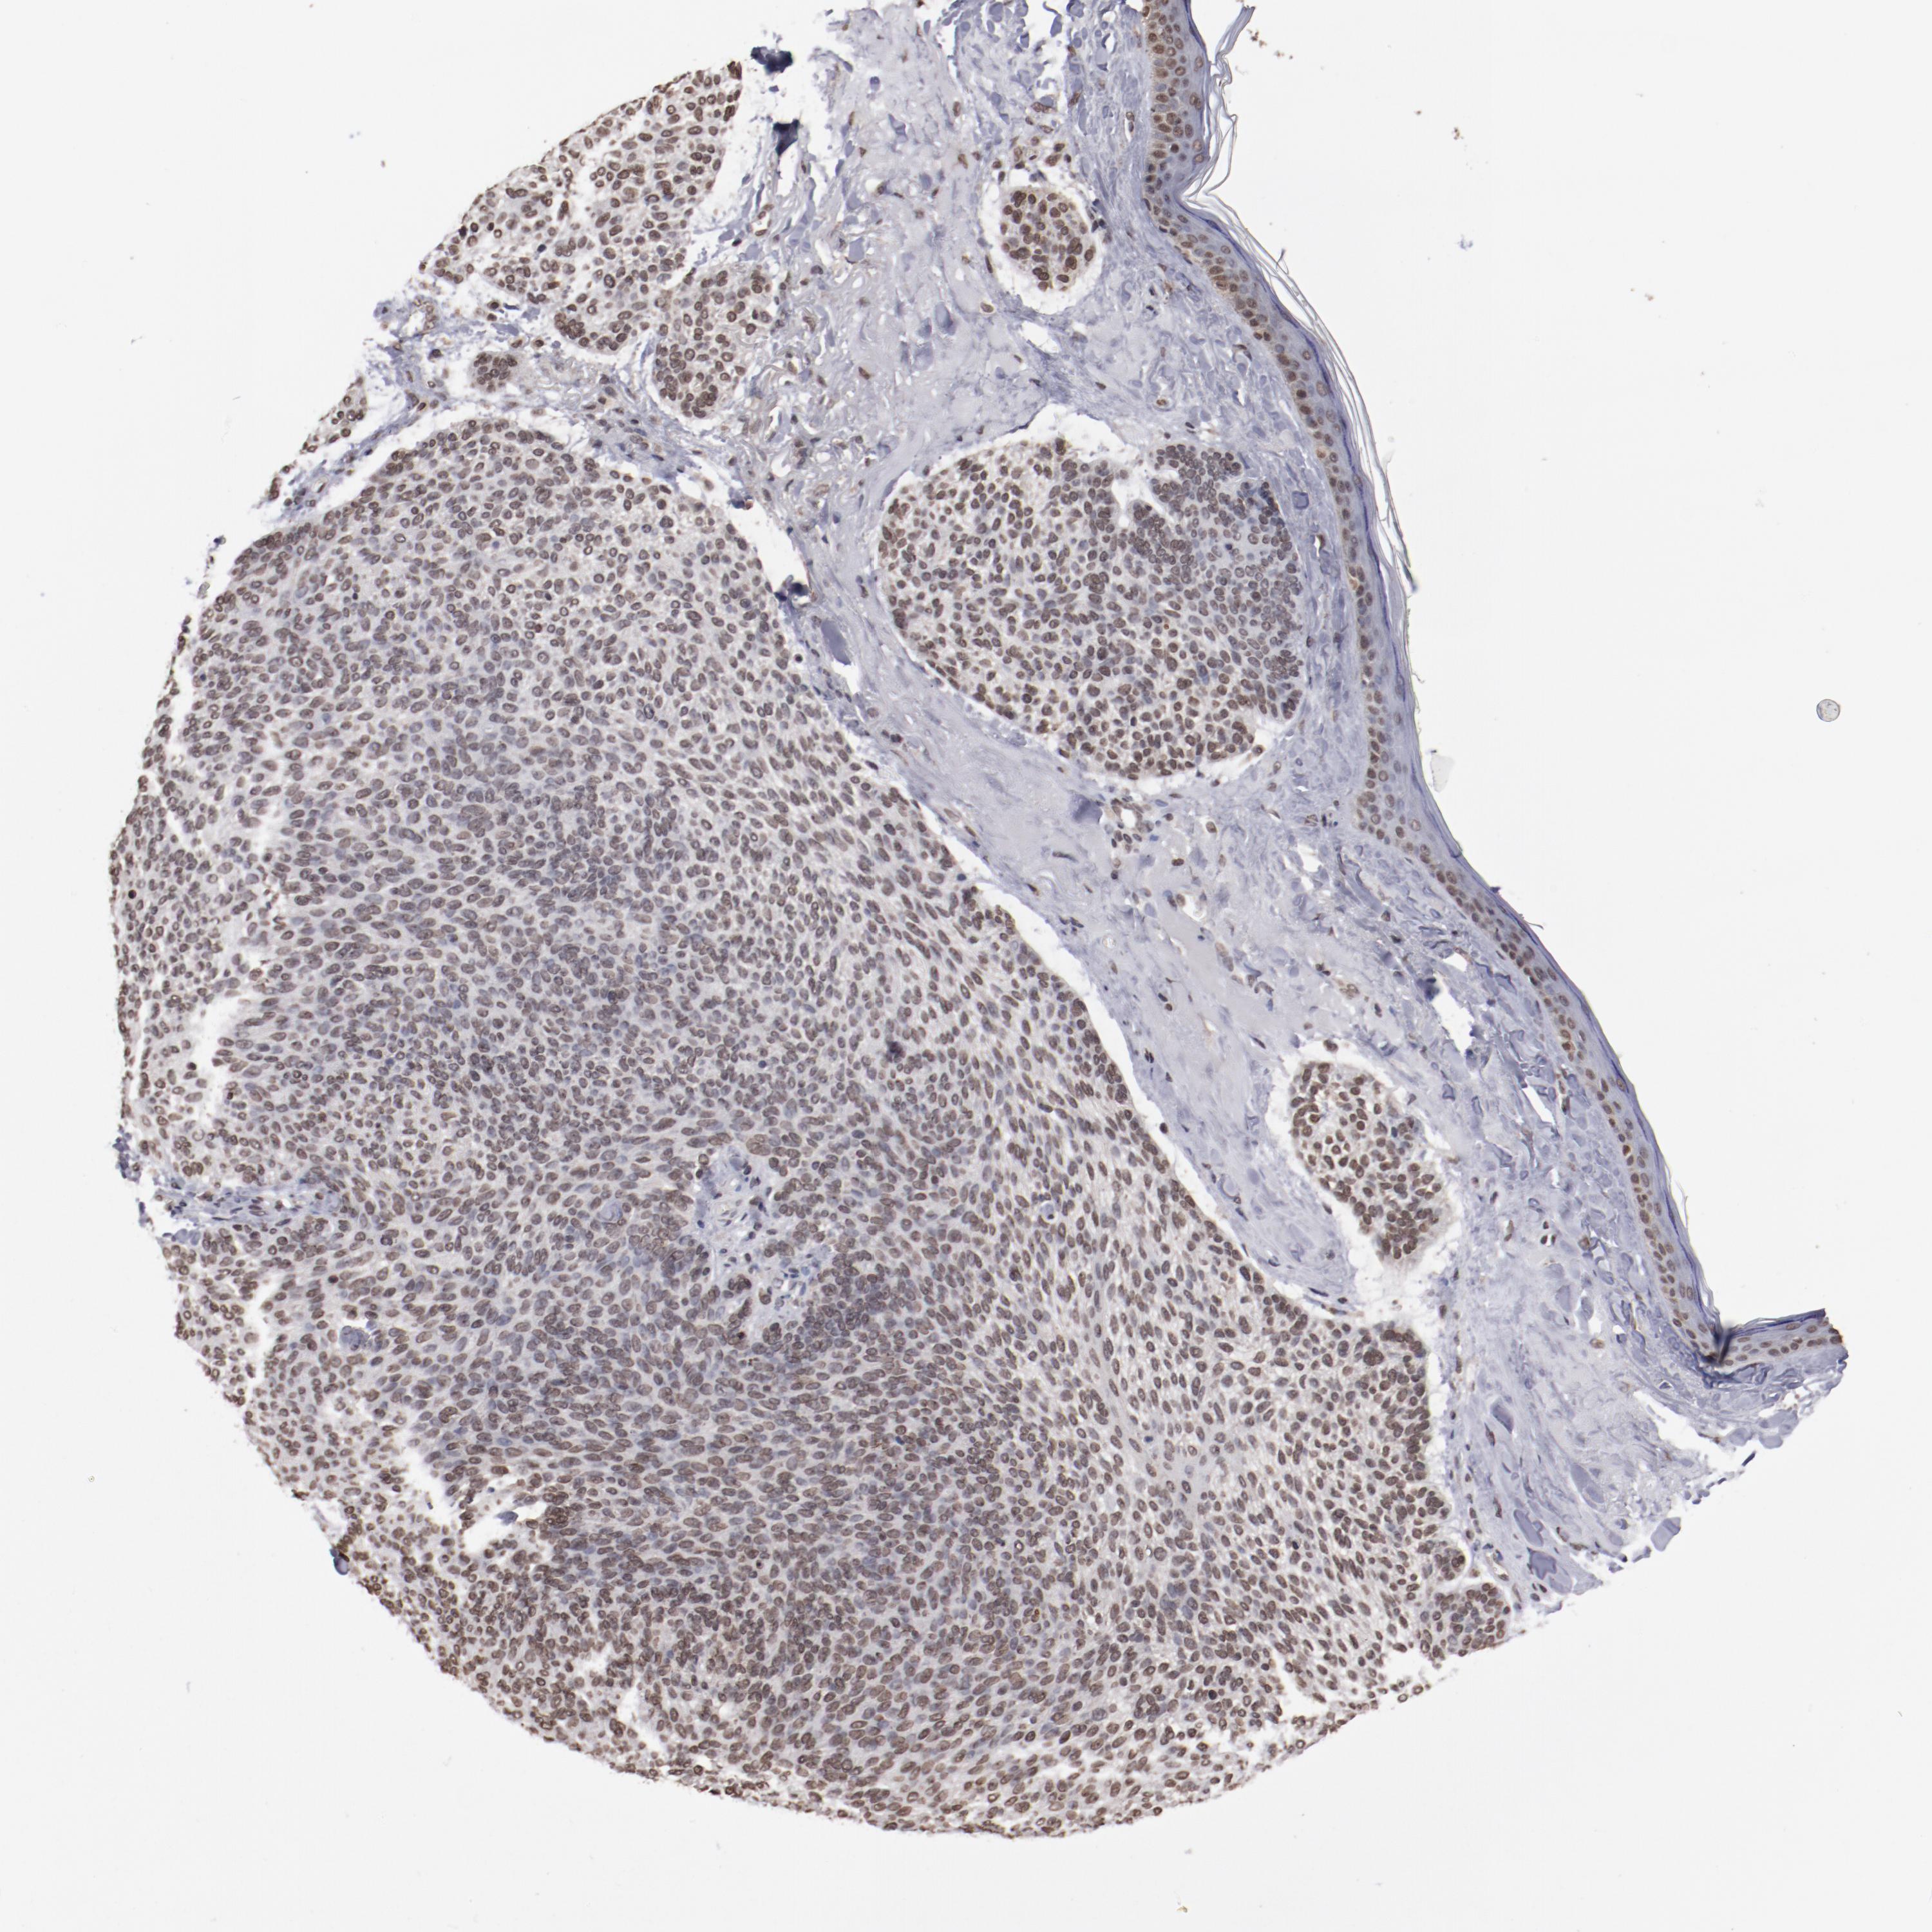

CANCER SKIN CANCER Show tissue menu

Basal cell and squamous cell cancer

SKIN CANCER - Protein expressioni

A mouse-over function shows sample information and annotation data. Click on an image to view it in a full screen mode. Samples can be filtered based on level of antibody staining by selecting one or several of the following categories: high, medium, low and not detected. The assay and annotation is described here.

Each image is clickable and will lead to virtual microscopy that enables deeper exploration of all samples and also displays staining intensity scores, fraction scores and subcellular localization as well as patient and tissue information for each sample.

Antibody HPA002891

Squamous cell carcinoma, NOS

Basal cell carcinoma